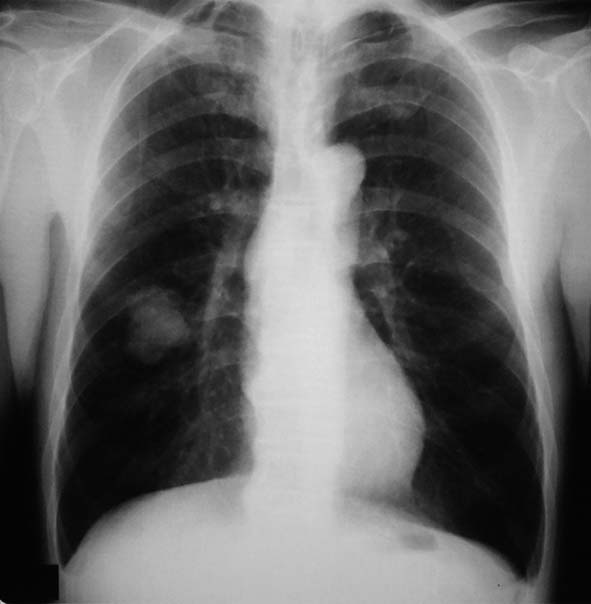

IWTcase 59 y.o.

健診で2年ほど肺異常陰影を指摘されていたが自覚症状なく放置. 陰影が次第に増大, 精査のため受診する.

右肺下葉, S6bを主体に一部S9に広がる4.2x3.7x2.5cmの腫瘤. 辺縁凹凸不整, 胸膜に接し内部には不整形の小石灰化がある.肺癌疑い.気管支鏡TBBでは組織片が採取できなかった.

PETで原発巣にSUV max2.2の淡い集積. リンパ節には集積なし. 遠隔転移なし. 肺癌としてはPET集積が淡いが, cT2/1N0M0の肺癌であればstage1B~2Aとなり根治切除可能のためCTガイド下生検が施行された.